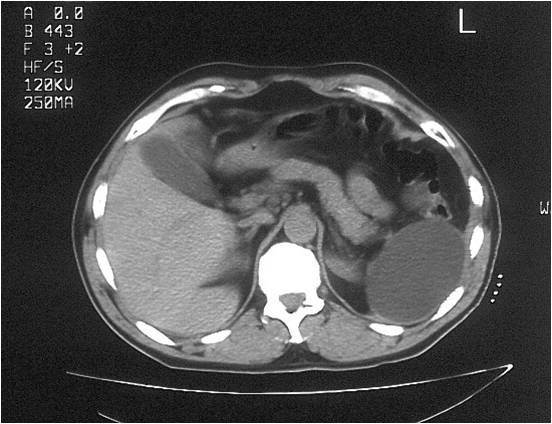

- Successful placement in sub-hepatic abscess post right hemicolectomy

- Large abdominal abscess post- pancreatic surgery

- Successful drainage